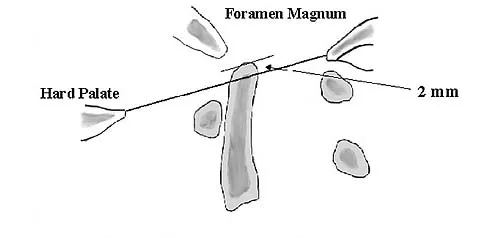

In Figure 49, line AB connects the anterior arch of C1 to the posterior margin of the foramen magnum. Line CD connects the anterior margin of the foramen magnum to the posterior arch of C1. What is the normal ratio of displacement from CD to AB (Power's ratio)?

Explanation